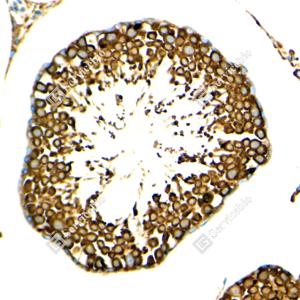

IHC检测GRP78 BiP蛋白(货号 GB15098). 样品: 小鼠睾丸, 4%多聚甲醛 (货号G1101) 固定12-24小时. 抗原修复: 柠檬酸抗原修复液(干粉, pH 6.0) (G1201), 高压锅均匀喷气计时2分钟. —抗: 1: 2000稀释, 4℃ 孵育过夜. 二抗: S-vision免疫组化多聚二抗(山羊抗小鼠), 即用型(货号G1301), 室温孵育20分钟. |